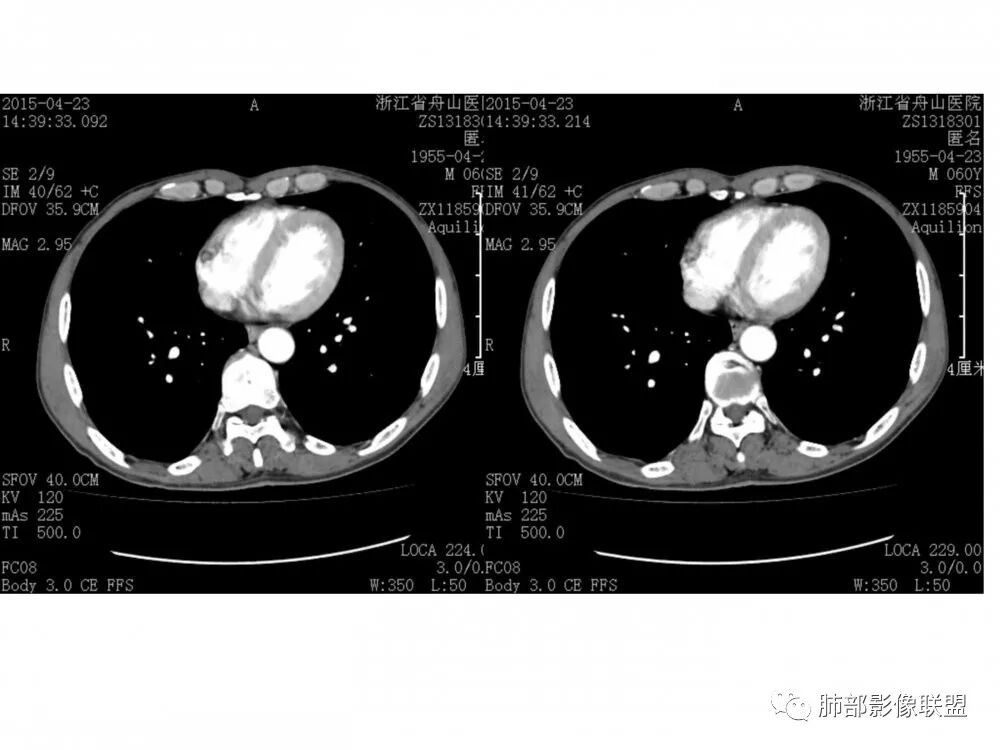

男,60岁,右肺下叶支气管开口新生物,轴位管腔及纵向基底干大部分受累狭窄,支气管管壁破坏并突破形成腔外肿块,强化较低不均匀,右肺门、7组、4R淋巴结肿大,考虑恶性没问题,鳞癌可能性大,类癌、粘液表皮样癌,乳头状瘤待排。

老年男性,右肺下叶支气管腔狭窄,见低强化软组织密度结节突向腔内,局部支气管壁破坏消失,邻近血管受压推移,纵膈内及右肺门区淋巴结肿大。综合考虑小细胞肺癌(SCLC)可能性大,鉴别类癌及鳞癌。

老年男性,右肺下叶支气管腔内可见软组织密度影,向腔内突入,支气管壁破坏,向外突出,管腔明显狭窄,增强后轻度强化,伴纵膈及肺门多发肿大淋巴结,首先考虑恶性肿瘤,小细胞肺癌可能大,建议支气管镜检查

右肺下叶支气管开口新生物,轴位管腔及纵向基底干大部分受累狭窄,支气管管壁破坏并突破形成腔外肿块,血管累及变细,肉眼观轻度强化,右肺门、纵膈淋巴结肿大,恶性没问题,阻塞性炎症不明显,类癌强化明显不支持,老年男性,首先考虑小细胞癌,鉴别不典型鳞癌和腺癌。

右肺下叶开口支气管内新生物,破坏管壁向腔外膨胀生长,累及各基底段开口,无明显坏死,有局部强化,远端无明显阻塞,右肺门及纵隔淋巴结肿大,考虑恶性肿瘤。大气道肿瘤不支持腺癌。小细胞癌大多为周围病灶引起肺门、纵隔淋巴结转移,肺门淋巴结明显肿大后侵犯支气管粘膜到达支气管内(从外到内),本例病灶从管腔内向腔外长,不支持小细胞癌。病灶为轻→中度强化,类癌显著强化为主→不支持,鳞癌、腺样囊性癌一般中度强化,鳞癌大多有阻塞性病变,本例无明显阻塞不支持鳞癌。粘液表皮样癌一般为轻度不均匀强化。感觉病灶为轻中度不均匀强化。综上首先考虑粘表,其次腺样囊性癌。待支气管镜活检明确。